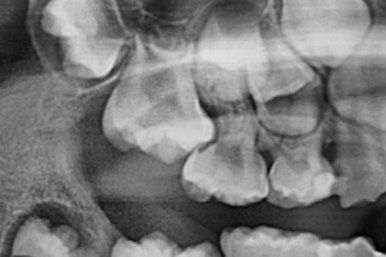

부산어린이치아교정 키다리아저씨치과에 처음 내원하셨을 당시의 X-ray 사진입니다.

이 때는 7세 3개월 때였습니다.

보통 만 6세 부터 아래 앞니 부터 영구치가 나기 시작하며, 비슷한 시기에 유치보다 더 뒤에 영구치 어금니가 나오게 됩니다.

이번 환자분은 제 나이보다는 치아나이가 어린편이어서 다른 부위의 어금니도 나오지 않았긴 하지만 치과 검진에서 우연히 해당부위(화살표)의 치아가 문제가 있음을 발견하셨던 경우입니다.

만 6세 이후 반드시 X-ray 찍어보시기를 추천드립니다.